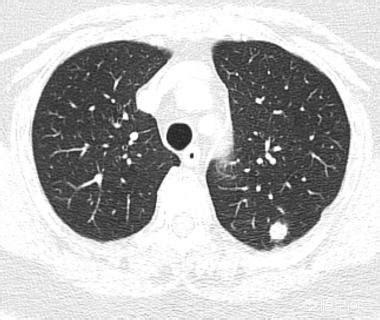

Der Pfeil zeigt auf den Knoten, der sehr klein war, als er im März 2016 entdeckt wurde, etwa 0,5 cm, und jetzt werden bei Routineuntersuchungen sehr viele Knoten wie dieser entdeckt.Es gibt keine Möglichkeit, auf den Bildern festzustellen, ob es gut- oder bösartig ist, sondern nur die Möglichkeit der Überprüfung, und die Überprüfung und Nachsorge ist auch das beste Mittel.